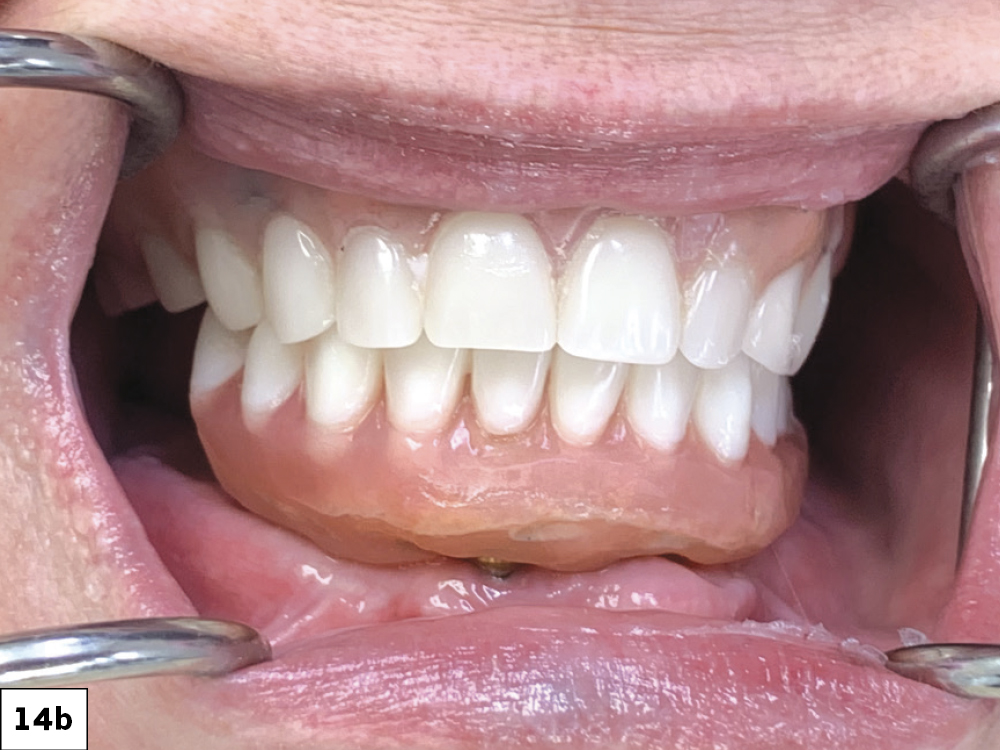

The completed Locator Fixed Prosthesis exhibits excellent stability during function (a). The completed Locator Fixed Prosthesis in occlusion (b). Panoramic X-ray of the seated mandibular prosthesis (c). The patient expressed her intention to address the maxillary arch at a later date.

Figures 14a–14c: The completed Locator Fixed Prosthesis exhibits excellent stability during function (a). The completed Locator Fixed Prosthesis in occlusion (b). Panoramic X-ray of the seated mandibular prosthesis (c). The patient expressed her intention to address the maxillary arch at a later date.